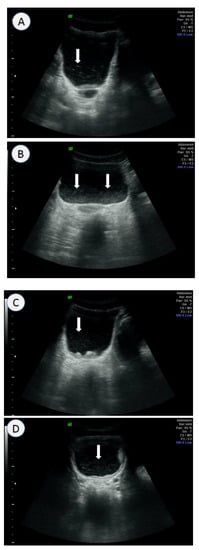

- Kim, M.J.; Hong, S.-T.; Jin, Y.; Ryu, K.; Kim, S.H.; Saeed, A.A.W.; Jeoung, H.G.; Lee, Y.H. Significance of echogenic snow sign as an ultrasonography finding for diagnosis of urogenital schistosomiasis. Am. J. Trop. Med. Hyg. 2016, 95, 842–848. [Google Scholar] [CrossRef]

- Bocanegra, C.; Pintar, Z.; Moreno, M.; Aznar, M.L.; Serres, X.; Sikaleta, N.; Salvador, F.; Nindia, A.; Molina, I.; Mendioroz, J.; et al. Ultrasound evolution of pediatric urinary schistosomiasis after treatment with praziquantel in a highly endemic area. Am. J. Trop. Med. Hyg. 2018, 99, 1011–1017. [Google Scholar] [CrossRef]

- Cozzi, D.; Bertelli, E.; Savi, E.; Verna, S.; Zammarchi, L.; Tilli, M.; Rinaldi, F.; Pradella, S.; Agostini, S.; Miele, V. Ultrasound findings in urogenital schistosomiasis: A pictorial essay. J. Ultrasound 2019, 23, 195–205. [Google Scholar] [CrossRef]